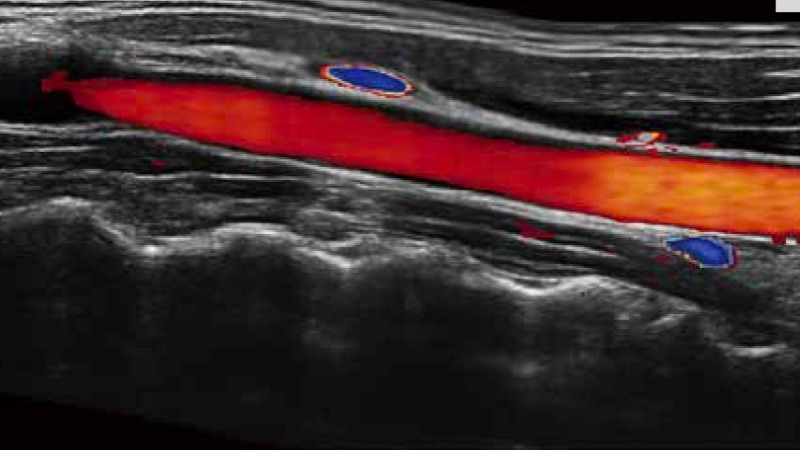

开立医疗通过不断的技术创新,为大众的生命健康提供持续关爱。P12 Plus采用全新一代超声成像平台,新平台旨在将真实还原组织解剖结构作为首要目标。平台采用全新集成化硬件模块,搭载新一代芯片,系统性能得到大幅提升,为您的诊断提供了丰富的临床信息。优异的图像表现,丰富的探头配置,全面的应用功能,为您日常诊断提供了可靠的助手。

凭借开立医疗先进的成像技术和优异的探头技术提供的清晰的图像表现,您可以更自信地做出临床决策。